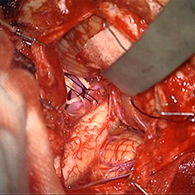

< 手術所見 >

左後下小脳動脈が左舌咽神経を圧迫していたために左咽頭部を中心に激しい痛みが生じていた。

舌咽神経への血管圧迫が解除されたため、術後に患者様は舌咽神経痛が消失した。